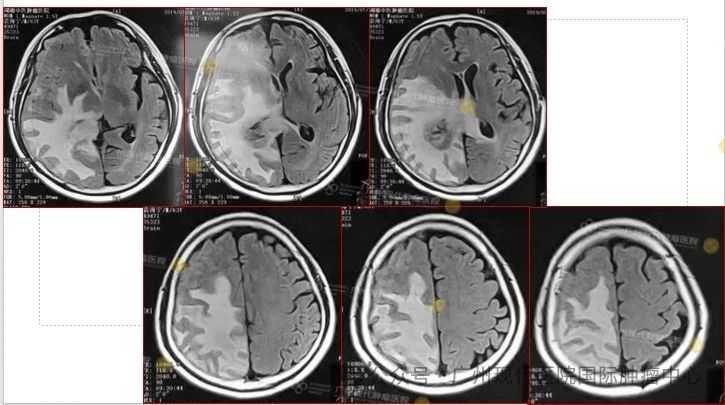

患者:63岁,男性

2013-11,体检发现肺部肿瘤,

2015-11,头颅MR检查提示颅内转移

2018-11,颅内肿瘤进展,无法接受后续治疗

2019-3,接受脑瘤粒子植入术

2019-7,颅内肿瘤基本消失,正常生活至今

2019年7月,颅内肿瘤已基本消失

患者与家属合照,至今正常生活